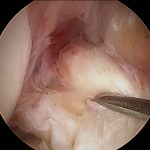

טיפול ניתוחי – שחזור רצועה צולבת

הטיפול המבוצע בקרע של רצועה צולבת הוא שחזור של הרצועה ולעיתים רחוקות מאוד תיקון שלה. שחזור של הרצועה הצולבת מבוצע בעזרת שתל גיד שיכול להיות ממקור עצמי של המנותח או מתורם. שתל הגיד העצמי לרוב נלקח מגיד ההמסטרינגס שנמצא בחלק האחורי של הברך או מהחלק האמצעי של גיד הפיקה. יש יתרונות וחסרונות לכל אחת מהשיטות וכדאי לדון על כך עם הרופא המנתח.